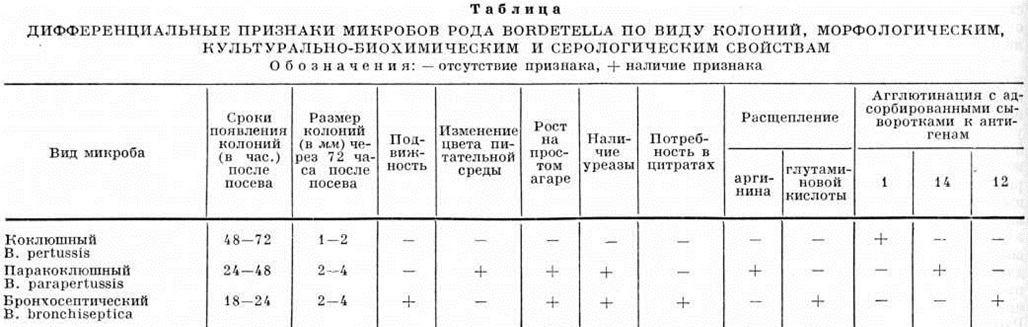

Бактериологические метод заключается в выделении возбудителя и его идентификации. Материалом для исследования служит слизь из верхних дыхательных путей, оседающая при кашле на задней стенке глотки. Взятие материала можно проводить тампоном (сухим или увлажнённым) и методом «кашлевых пластинок». Материал, собранный тампоном, засевается на поверхность питательных сред (среда Борде — Жангу, молочно-кровяной агар, казеиново-угольный агар), разлитых в чашки Петри. Для подавления роста сопутствующей микрофлоры применяют пенициллин или бициллин, которые наносят на поверхность питательной среды или добавляют в среду. Метод «кашлевых пластинок» заключается в следующем: в момент кашля перед ртом больного на расстоянии 6—8 сантиметров держат в течение 10—20 секунд открытую чашку Петри с одной из сред. Посевы помещают в термостат на 2—3 суток при t° 35—37°. Так как колонии коклюшного микроба очень мелкие, то чашки с посевами надо просматривать с помощью бинокулярного стереоскопического микроскопа. При наличии на чашках подозрительных колоний выделяют чистую культуру путём отсева их на скошенный агар или в чашки Петри с одной из питательных сред» Из оставшихся колоний делают мазки, красят по Граму и изучают над микроскопом. Кроме того, можно поставить реакцию агглютинации на стекле с агглютинирующей неадсорбированной коклюшной сывороткой или с адсорбированными сыворотками к видовым антигенам, условно обозначенными 1, 14 и 12, для дифференциации вида выделенного микроба: коклюшного, паракоклюшного и бронхосептического. Идентификацию культуры коклюшной палочки от других микробов рода Bordetella (смотри полный свод знаний) проводят по виду колоний, морфологии, культурально-биохимическим и серологическим свойствам (таблица).